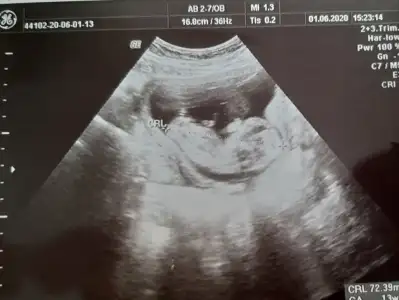

dr soylemeden siz gorun genital nub teorisi ( bebegin cinsiyeti)

13+5 ultrason görüntüsü, bizi de tahmin eder misiniz :)